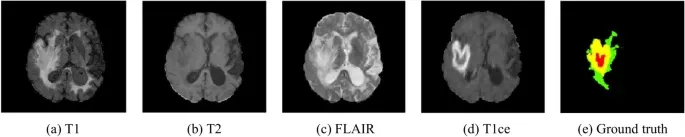

3-1. T1 강조 영상 (T1-Weighted Image, T1WI)

▶ 강조 특징: T1 이완 시간의 차이를 가장 잘 반영하도록 만든 영상입니다.

▶ 신호 특징:

- T1이 짧은 조직 (빨리 회복) →고신호 강도 (밝게) 보입니다. (예: 지방, 아급성 출혈, 낭종 속 고단백 물질)

- T1이 긴 조직 (느리게 회복) → 저신호 강도 (어둡게) 보입니다. (예: 물, 뇌척수액(CSF), 부종, 대부분의 종양)

- 근육은 중간 정도의 신호 강도를 보입니다.

- 골피질이나 혈류가 빠른 혈관은 T1에서도 T2에서도 저신호로 보입니다.

▶ 주요 활용: 해부학적 구조를 파악하는 데 유용하며, 조영제(Gd)를 투여하여 병변을 강조할 때 기본이 됩니다.

3-2. T2 강조 영상 (T2-Weighted Image, T2WI)

▶ 강조 특징: T2 이완 시간의 차이를 가장 잘 반영하도록 만든 영상입니다.

- T2가 긴 조직 (느리게 감쇠) → 고신호 강도 (밝게/희게) 보입니다.

(예: 물, 부종, 염증, 낭종, 대부분의 병변 → 수분 함량이 많음)

- T2가 짧은 조직 (빨리 감쇠) → 저신호 강도 (어둡게/검게) 보입니다.

(예: 근육, 섬유성 결합 조직, 급성 출혈, 고단백 낭종)

- 지방은 T2가 T1보다 약간 길어 T2 강조 영상에서도 밝게 보입니다. (하지만 일반적으로 T2는 물이 가장 밝습니다.)

▶ 주요 활용: 병변(특히 수분을 많이 포함한 부종, 염증, 종양)을 찾는 데 가장 중요하며, 병변의 유무와 범위를 파악하는

데 필수적입니다.

3-3. FLAIR 시퀀스 (Fluid Attenuated Inversion Recovery)

▶ 강조 특징 (Emphasis Feature)

▶ 기본 강조: T2 강조 영상입니다. (따라서 T2 이완 시간이 긴 부종이나 염증은 밝게 보임)

▶ 핵심 원리: IR (Inversion Recovery, 역전 회복) 펄스 시퀀스를 사용하여 정상 CSF의 T1 신호를 억제합니다.

3-5. T1 Contrast-Enhanced (T1CE)

(추후 추가 예정)

| MRI 시퀀스 | 신호 특성 | 용도 |

| T1 강조 영상 (T1-weighted) | 물(CSF)은검게(저신호), 지방/급성 출혈/조영제는밝게(고신호) | 해부학적 구조를 보는 데 좋습니다. |

| T2 강조 영상 (T2-weighted) | 물(CSF)은밝게(고신호), 대부분의 병변이나 부종도 밝게 보입니다. | 병변의 범위를 파악하는 데 유용합니다. |

| FLAIR (Fluid-Attenuated Inversion Recovery) | T2 영상과 유사하지만,정상 뇌척수액(CSF)의 신호를 억제하여 검게 만듭니다. | 뇌실 주변이나 피질 주변의 병변(특히 부종이나 저등급 Glioma)이 더욱 명확하게 드러납니다. |

| DWI | 물 분자의 확산 운동이 심하게 제한된 부위 (Diffusion Restriction)가 영상에서 밝게 (Hyperintensity) 강조됩니다. | 급성 허혈성 뇌졸중 (물 분자가 세포 안으로 몰려 확산이 제한됨)의 초조기 진단 및 고세포성 종양의 감별에 사용됩니다. |

| T1 Contrast-Enhanced (T1CE) |

가돌리늄 조영제를 정맥 주사 후 촬영. 종양 세포 주위의 혈관-뇌 장벽(BBB)이 파괴된 부위에 조영제가 모여 영상에서 밝게 강조(Enhancement) | 종양의 실제 범위와 경계를 가장 명확하게 보여줍니다. (1단계에서 배운 T1CE의 핵심 원리 복습) |